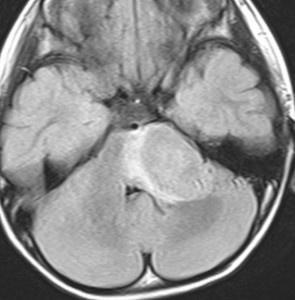

- MRIでは脳幹部(とくに橋)が腫れて大きくなります

- 多くの場合は左右対称ですが,非対称のものもめずらしくありません

- MRIのFLAIR(フレア)画像とかT2強調画像で,白くぼーっと滲んだように映ります

- 脳幹部の橋というところを中心にして発生し,上方の中脳や下方の延髄に浸潤して伸びていきます

- 腫瘍は大きいのですが,水頭症にならないのが特徴です(水頭症は2割くらい)

- 上の写真の例では,症状は軽く,たいていの場合はこのくらいの大きさになってから発見されます

- 腫瘍の前方の中心に黒い点のようなものが見えますが,これは脳底動脈で,この脳底動脈の囲い込み engulfment は,DIPGに特徴的なものといえます

- 腫瘍の一部分だけが脳幹部から突出してキノコのように伸びる所見 exophytic grwoth は2割くらいにみられます